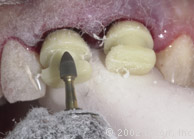

Подготовка к установке постоянной конструкции

Произведены послабляющие разрезы

Установка готовых конструкций